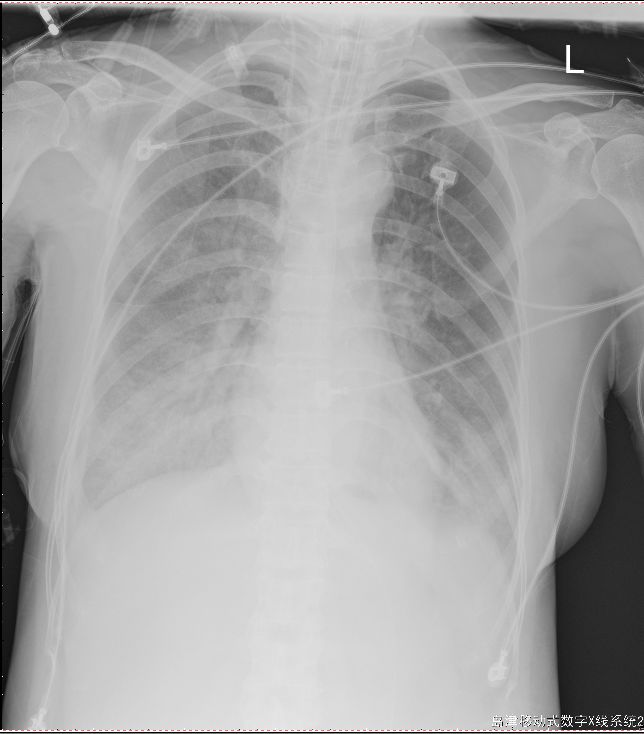

图16-2 复查胸片“两中下肺渗出较前稍增多,两侧胸腔少量积液,右侧较前增多”

考虑呼吸机相关肺损伤(VILI)和生物伤同时存在,为加强肺保护通气策略,行俯卧位通气同时加强气道引流等,共连续行PPV 5次,每次16小时左右,俯卧位通气治疗后OI显著升高(图16-3)。